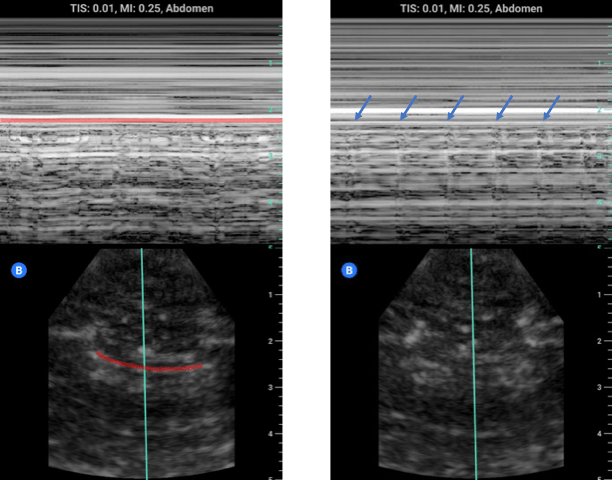

M-Mode and Pleural Sliding: In addition to B-mode imaging, M-mode can be used to assess for the presence of pleural sliding and lung pulse. In the image above on the left we see M-mode being used on a shallow lung view with the pleural line highlighted in red. Note the static soft-tissue/intercostal muscles above the line create layers of horizontal lines whereas BELOW the pleural line there is a scattered random pixel pattern. This is due to the motion of the intact pleural interface and the scatter from the lung parenchyma colloquially referred to as “sea shore” sign where the lung is the sand and the soft tissue the water. Even if the lung is not moving there should still be movement of the pleura from the heart/aorta creating a lung pulse which can be seen below the blue arrows.